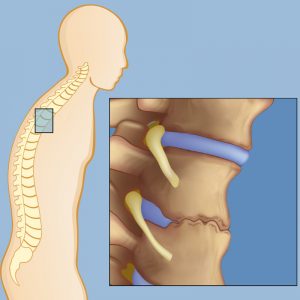

Что такое спондилолистез с точки зрения нейрохирургии? Если учесть, что сдавливающим фактором нервных и сосудистых разветвлений позвоночного канала является смещенная дужка надлежащего и подлежащего позвонкового тела, то объектом для лечения (операции) спондилолистеза являются пациенты без разобщения задней дужки и компримирующего тела смещенного позвонка.